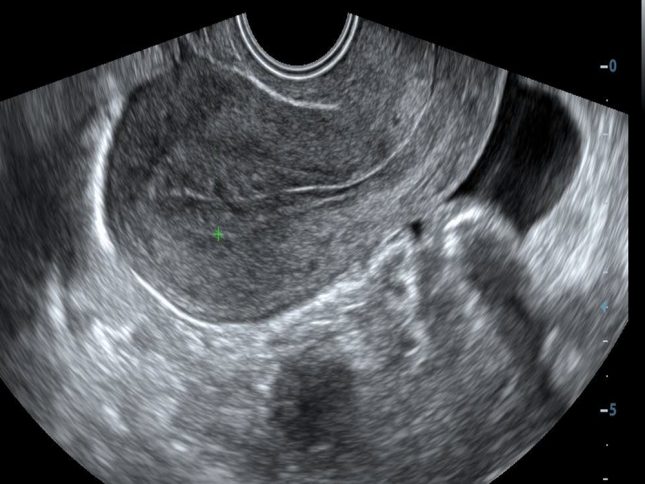

אולטרסאונד-של-רחם.-אילוסטרציה

במחקר רטרוספקטיבי זה נכללו נשים בהריון עם שני CL עוקבים שנמדדו באמצעות סונוגרפיה טרנסווגינלית בשבועות 14-16 (CL1) ו-21-24 (CL2). הרשומות הרפואיות האלקטרוניות נבדקו עבור היסטוריה דמוגרפית, רפואית ומיילדותית, סיבוכי הריון נוכחי ונתונים על אופן הלידה. CL1, CL2 וההבדלים בין הסריקות נמדדו והוכנסו לקורלציה עם PTD.